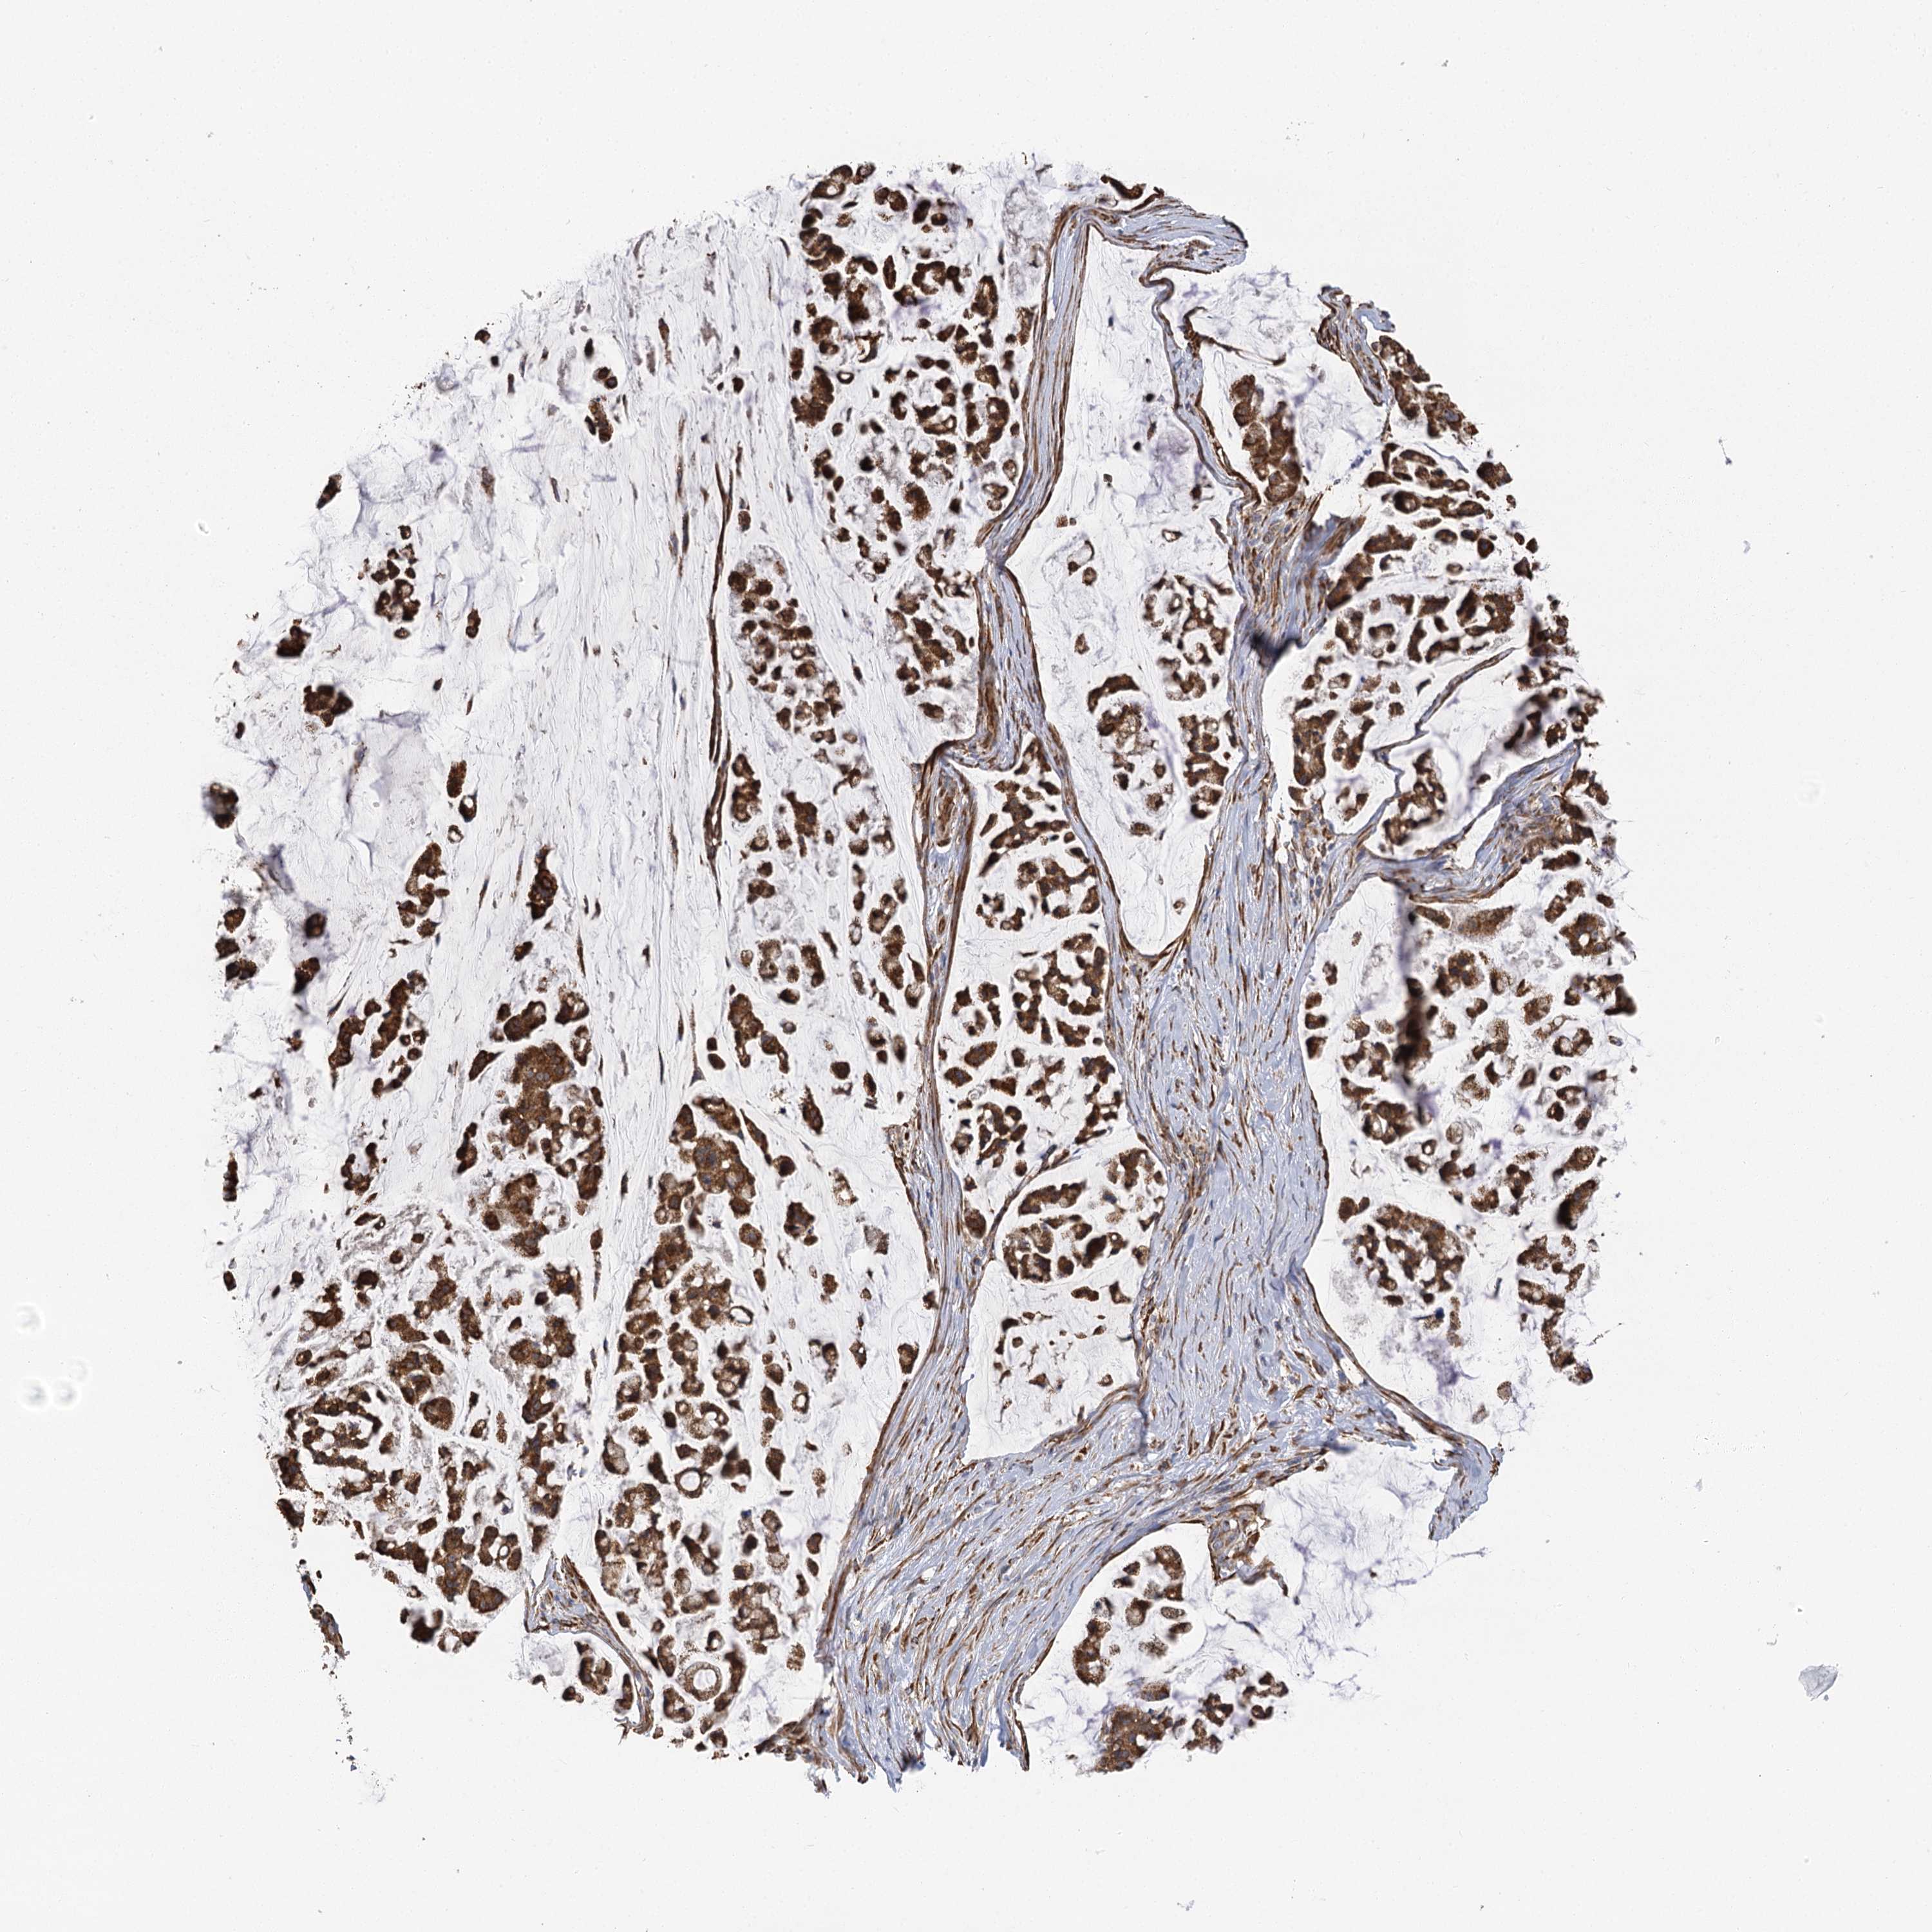

STOMACH CANCER - Protein expressioni

A mouse-over function shows sample information and annotation data. Click on an image to view it in a full screen mode. Samples can be filtered based on level of antibody staining by selecting one or several of the following categories: high, medium, low and not detected. The assay and annotation is described here.

Note that samples used for immunohistochemistry by the Human Protein Atlas do not correspond to samples in the TCGA dataset.

Antibody stainingi

Antibody staining in the annotated cell types in the current human tissue is reported as not detected, low, medium, or high, based on conventional immunohistochemistry profiling in selected tissues. This score is based on the combination of the staining intensity and fraction of stained cells.

Each image is clickable and will lead to virtual microscopy that enables deeper exploration of all samples and also displays staining intensity scores, fraction scores and subcellular localization as well as patient and tissue information for each sample.

Antibody HPA013162

Antibody HPA036652

Antibody CAB032830

Staining

High

Medium

Low

Not detected

Intensity

Strong

Moderate

Weak

Negative

Quantity

>75%

75%-25%

<25%

None

Location

Nuclear

Cytoplasmic/membranous

Cytoplasmic/membranous,nuclear

Adenocarcinoma, NOS

Adenocarcinoma, High grade